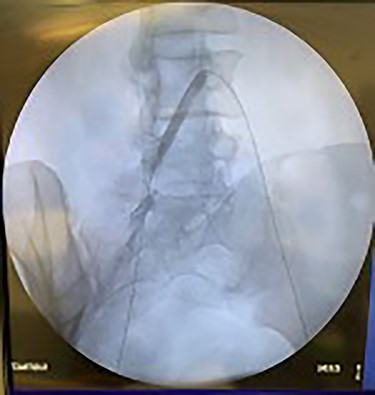

Catheter arteriogram results showed significant occlusion of the left iliac artery (Figs 3 and 4), the right iliac artery (Fig. 1), as well as the distal abdominal aorta (Fig. 2). There were numerous collateral vessels noted, indicating the presence of long-standing proximal stenosis (Fig. 1). The decision was made to use angioplasty to help widen the areas of stenosis. An 8 mm × 40 mm Passeo balloon was advanced from the right femoral artery into the left iliac artery (Fig. 7) and insufflated to 6 mmHg (Fig. 6). The balloon was allowed to remain expanded for 1 min and then was deflated. Next, the distal aorta was repaired in a similar fashion. The balloon was advanced into the distal aorta from the right femoral access and insufflated to 12 mmHg (Fig. 8). The balloon was allowed to remain expanded for 90 s.

Fluoroscopy of right iliac artery showing vast collateral vascular formation, indicating long-standing proximal obstruction.